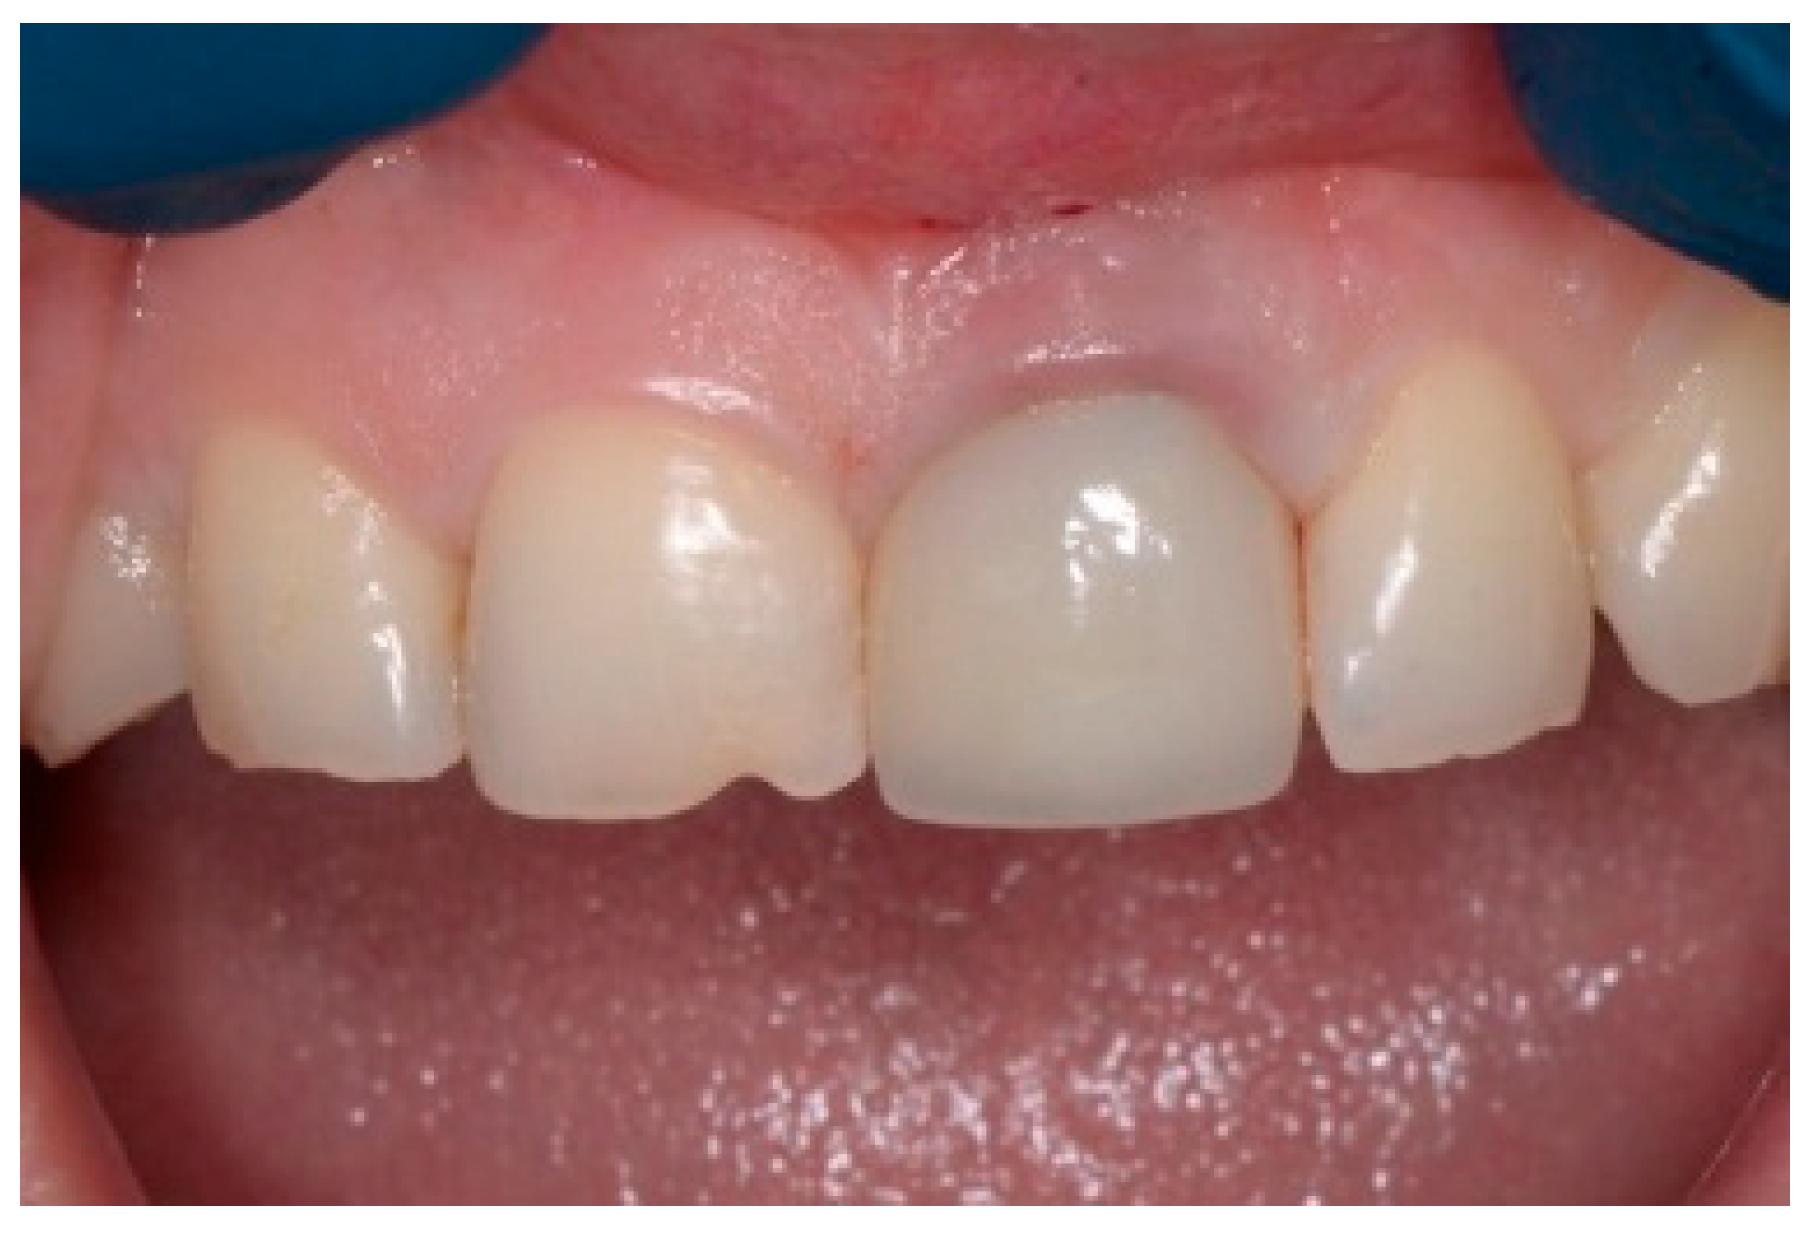

Following a 6-month healing period (Figure 6), definitive prosthetic rehabilitation was carried out using zirconia CAD CAM abutments (Straumann, Andover, MA 01810, USA). The ceramic zirconia crowns of teeth 8 and 9 were placed (Figure 7). At the two-year follow-up examination for patients #1 and #3 and three-year for patients #2 and #4, the implants were fully osseointegrated, presenting satisfactory functional and esthetic conditions without clinical or radiographic signs of any pathology.

Figure 6.

Clinical view of the implant site before final restoration.

Figure 7.

Clinical view of final ceramic crowns on teeth 8 and 9.